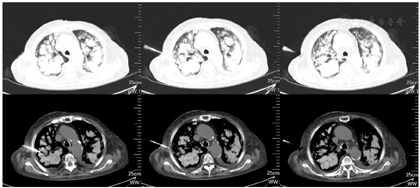

钙离子(我院2020年12月17日):3.91mmol/L。钙离子(我院2021年4月17日):3.5mmol/,多次复查钙离子明显升高。血气分析(2021年4月22日未吸氧):PH 7.48,PaCO2 37mmHg,PaO2 58mmHg,HCO3-:27.6mmol/L,BE 4.1mmol/L,Lac 1.6mmol/L,K+ 4.1mmol/L,THbc 84g/L。骨代谢六项:降钙素3.87pg/ml,甲状旁腺素46.00pg/mL,β-胶原降解产物2.480ng/mL,总I型胶原氨基端延长肽315.000ng/mL,骨钙素47.700ng/mL,25羟维生素D 4.700ng/ml;甲功八项:甲状腺过氧化物酶抗体(ATPO) 10.80U/ml,甲状腺球蛋白抗体(ATG)>4000U/mL,甲状腺球蛋白(TG) 0.20ng/ml,三碘甲腺原氨酸(TT3) 1.30nmol/L,甲状腺素(TT4) 46.80nmol/L,游离T3(FT3) 2.48pmol/L,游离T4(FT4) 6.69pmol/L,高灵敏促甲状腺素(TSH) 9.470mIu/L;肿瘤标志物全套(女):肿瘤相关抗原125(CA125) 52.70U/ml,肿瘤相关抗原153(CA15-3) 31.90U/ml,细胞角蛋白19片段(Cyfra211) 2.78ng/ml,异常凝血酶原(PIVKA-Ⅱ) 32.700mAU/ml,β2-微球蛋白(β2-MG) 3.04μg/mL,人绒毛膜促性腺激素(HCG) 7.54mlU/ml,绝经前ROMA值(Pre-ROMA) 97.19%,绝经后ROMA值(Post-ROMA) 81.68%,胃泌素释放肽前体(ProGRP) 279.0pg/ml。胸部平扫CT(我院2020年12月18日图1):右肺中叶及左肺下叶结节,右肺钙化灶。气管及主支气管管壁钙化。胸部平扫CT(我院,2021年4月19日图2):两肺见弥漫性、松散性沿支气管及血管分布的结节状及团片状高密度影,以两肺上叶为著,呈对称性改变,纵隔窗大部分病灶已实变,CT值约为100HU。胸部增强CT(我院,2021年4月25日):两肺见弥漫性、松散性沿支气管及血管分布的团絮状、棉花团样密度增高影及磨玻璃密度影,以两肺上叶为著,呈对称性改变,纵隔窗大部分病灶已实变,CT值约为100HU,增强扫描动脉期CT值约127HU,静脉期CT值约111HU。诊断提示:两肺代谢性疾病,考虑转移性肺钙化。PET/CT提示双肺改变考虑非肿瘤性病变,不除外肺泡蛋白沉积症可能,建议相关检查。电子支气管镜检查,镜下未见明显异常(图3),肺泡灌洗液色清亮。右肺上叶灌洗液送检脱落细胞回报示标本内见噬细胞、偶见上皮细胞,未见到恶性细胞。灌洗液病原微生物宏基因检测回报示白色念珠菌(序列数:4091)、光滑念珠菌(序列数:726)、EB病毒(序列数:33)。2021年5月11日行CT引导下经皮肺穿刺活检(图4),于右肺上叶穿刺获得2条约2.3cm长暗红色肺组织,送检肺组织常规病理及病原微生物宏基因检测。病理回报示(右肺上叶)肺泡结构破坏,肺间质纤维母细胞增生,有淋巴细胞、浆细胞浸润,其内见网络样钙化,局部见有机化及玻璃样变,并见有增生的肺泡上皮,细胞有异型,胞浆嗜酸,考虑为反应性增生,病变形态不能除外转移性钙化引起的弥漫性肺泡损伤性病变,请结合临床(图5)。肺组织病原微生物宏基因检测回报示白色念珠菌(序列数:1)、EB病毒(序列数:1)。全身骨显像示双肺弥漫性高密度伴放射性浓聚,考虑转移性钙化,结合临床资料,首先考虑肺泡微石症,肿瘤性疾病待排。甲状旁腺显像未见明显异常。

本病例存在以下两个特点:1.肺部影像学表现重,双肺多发高密度影,沿支气管及血管分布,以两肺上叶为著,小叶中心分布为主,部分存在实变。具有且弥漫性、对称性的特点。2.对比2020年12月17日及2021年4月19日两次胸部平扫CT,可见肺部影像学快速进展,但咳嗽、咳痰及活动后呼吸困难症状较前未见明显加重。入院后高度怀疑原发肺癌或转移性肺癌,考虑到患者81岁,心肺功能差,建议患者完善PET/CT密切病变性质,结果回报示双肺改变考虑非肿瘤性病变,不除外肺泡蛋白沉积症可能。胸部增强CT及全身骨扫描考虑转移性肺钙化。笔者认为病理是诊断转移性肺钙化的金标准,遂利用呼吸介入手段尽早行肺活检。患者81岁,存在I型呼吸衰竭,心功能欠佳,对气管镜操作医生要求极高。我中心呼吸内镜医生完成气管镜常规检查及肺泡灌洗后,患者出现血氧降低,未能通过气管镜获得肺活检标本。气管镜灌洗液病原微生物高通量测序提示白色念珠菌、光滑念珠菌、EB病毒感染,但不考虑引发此影像学改变。后续通过CT引导下经皮肺穿刺活检获得病理,病理结果不除外转移性钙化。综合患者病史,胸部增强CT、全身骨显像及病理结果,可明确诊断为转移性肺钙化,但病因尚不明确。患者无透析、器官移植病史,甲状旁腺功能及甲状旁腺显像未见明显异常,可除外原发性或继发性甲状旁腺功能亢进。患者既往因肌酐升高,4个月前于我院诊断为慢性肾脏病,但本次入院多次复查肾功能均为正常。根据骨代谢六项结果,及血钙、血磷趋势,不支持为慢性肾脏病所致转移性钙化。因患者年龄较大,给予降低血钙后,血钙维持在正常范围内,症状较前缓解,建议患者出院观察,定期复查胸部CT及钙离子。